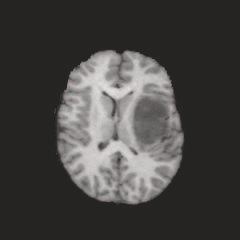

Multi-modal medical image completion has been extensively applied to alleviate the missing modality issue in a wealth of multi-modal diagnostic tasks. However, for most existing synthesis methods, their inferences of missing modalities can collapse into a deterministic mapping from the available ones, ignoring the uncertainties inherent in the cross-modal relationships. Here, we propose the Unified Multi-Modal Conditional Score-based Generative Model (UMM-CSGM) to take advantage of Score-based Generative Model (SGM) in modeling and stochastically sampling a target probability distribution, and further extend SGM to cross-modal conditional synthesis for various missing-modality configurations in a unified framework. Specifically, UMM-CSGM employs a novel multi-in multi-out Conditional Score Network (mm-CSN) to learn a comprehensive set of cross-modal conditional distributions via conditional diffusion and reverse generation in the complete modality space. In this way, the generation process can be accurately conditioned by all available information, and can fit all possible configurations of missing modalities in a single network. Experiments on BraTS19 dataset show that the UMM-CSGM can more reliably synthesize the heterogeneous enhancement and irregular area in tumor-induced lesions for any missing modalities.